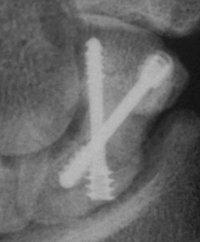

Case 7. This nonunion patient's scaphoid and iliac crest were unusually soft bone.

Click for larger image

After two screws, the fixation was clearly inadequate, so I put a third screw through the graft into the proximal pole. I wasn't sure whether to buy

stock in Herbert screws or Zantac. The fracture healed despite AWOL and no immobilization.